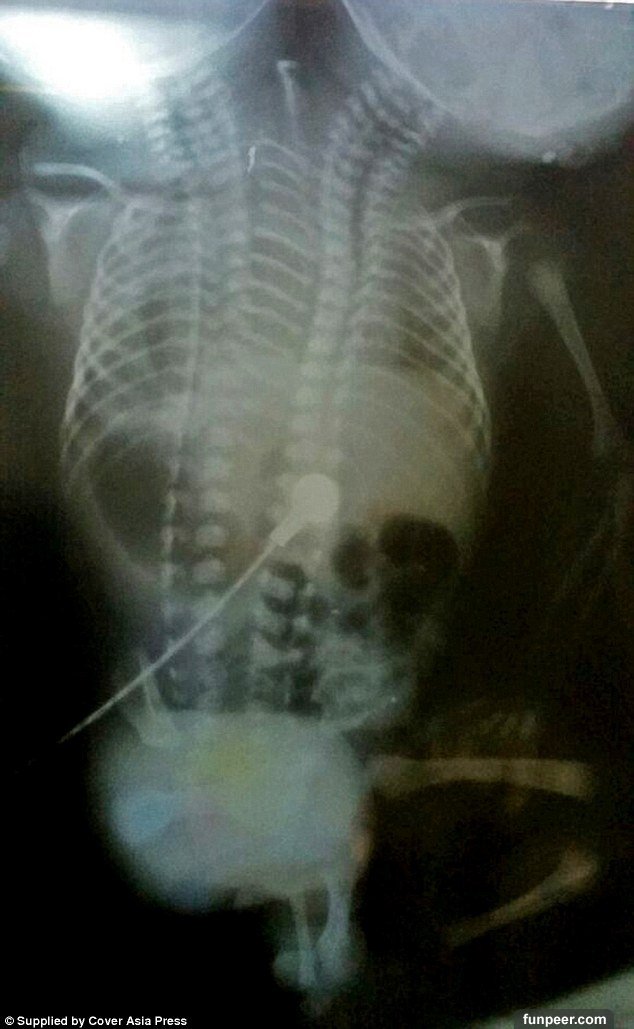

不過後來這個男嬰開始有嚴重的呼吸問題。那拉揚醫生考慮過要不要進行分離手術,但最後認為那幾乎不可能而放棄。因為男嬰是所謂的寄生式連胎 (Parapagus),雖然內臟都有雙倍,但卻共用同一個身體,只有一對手腳。